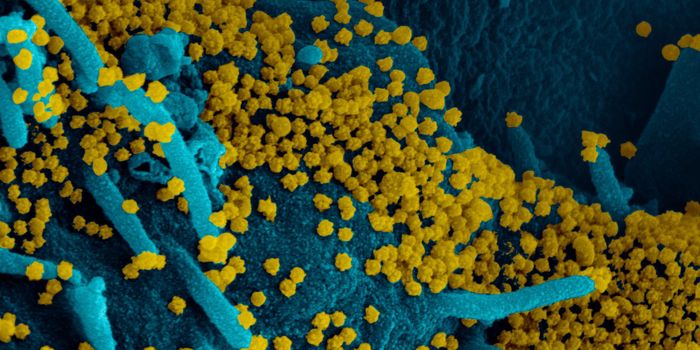

MAR 22, 2020MicrobiologyMore data is being gathered from an unfortunate and dramatic rise in the number of COVID-19 cases around the world.

APR 01, 2020MicrobiologyThere are a couple of different kinds of tests that researchers will be developing and clinicians will be using to disru ...

MAY 03, 2020Genetics & GenomicsThe origin of SARS-CoV-2, the pandemic virus that causes COVID-19, has become politicized as leaders seek to place blame ...

JUL 06, 2020MicrobiologyThe pandemic coronavirus has caused a wide range of different symptoms, and as time goes on, we may find that it can hav ...

JUL 05, 2020Cell & Molecular BiologyThe pandemic virus SARS-CoV-2 enters the body through the respiratory system to cause the illness COVID-19. But we know ...